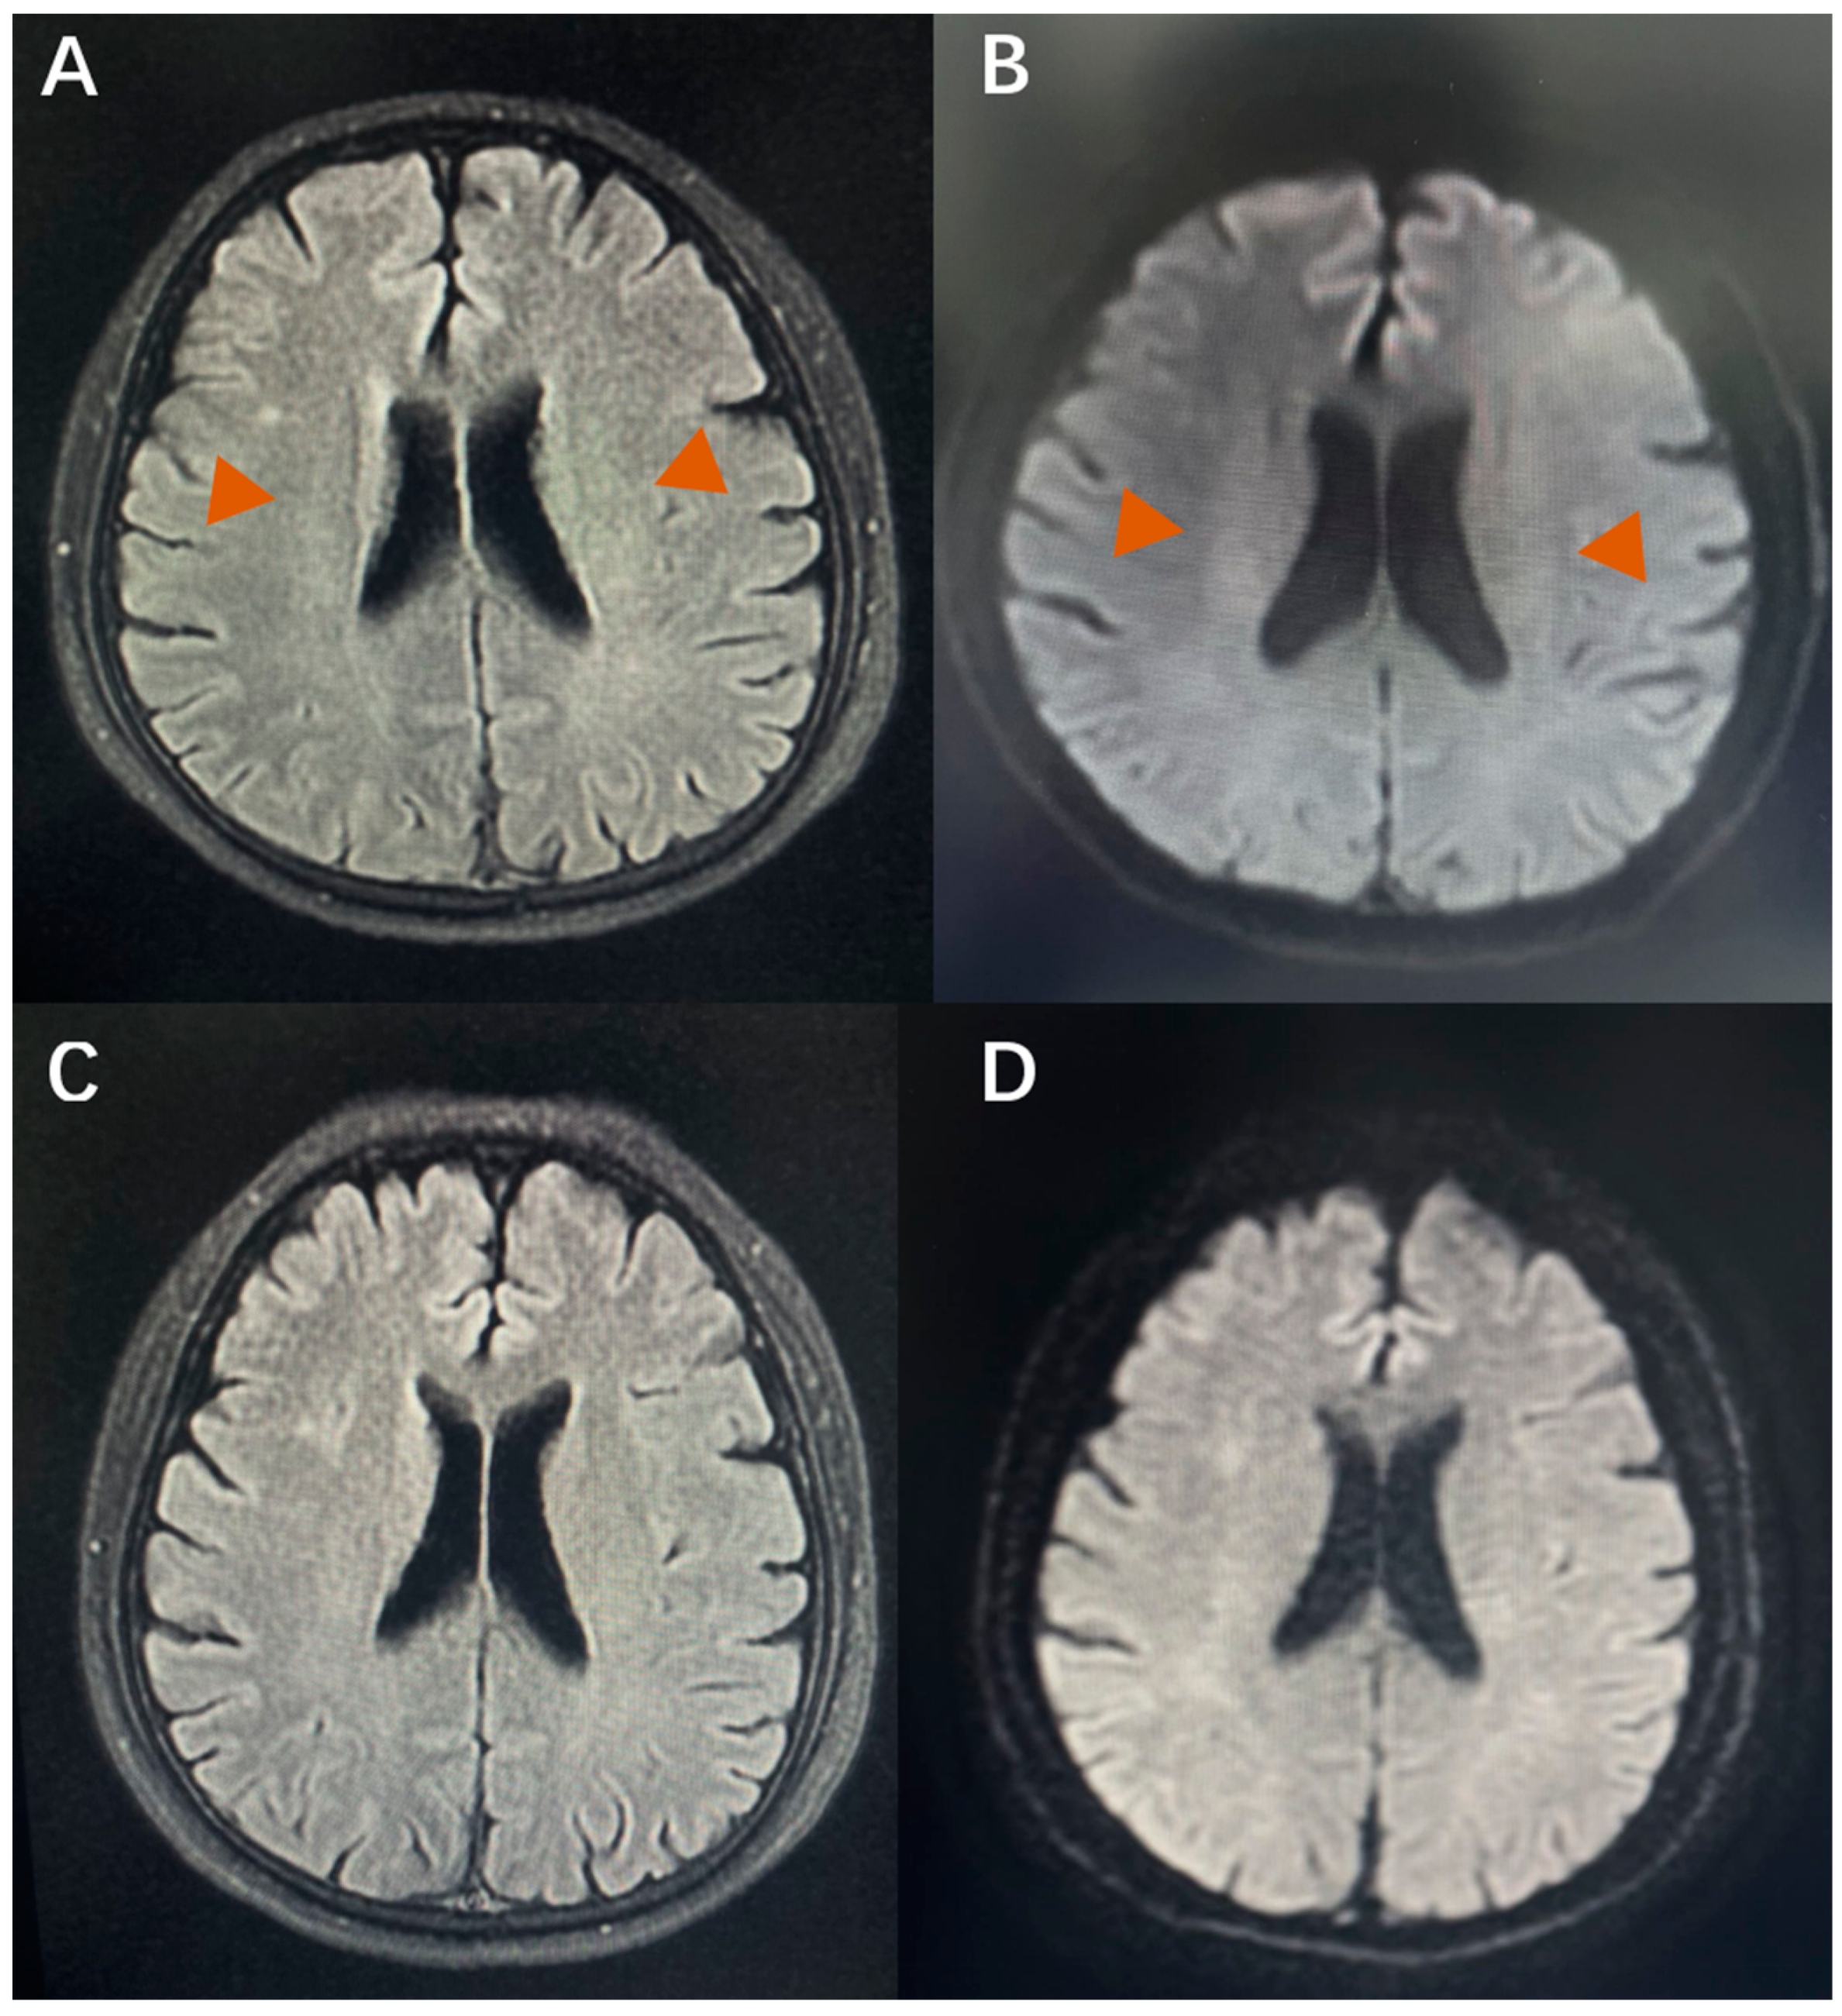

3.3. CVOD-Associated Anxiety and Depression and WMLs

3.5. Severity of CVOD-Associated Anxiety and Depression Pre-Stenting vs. Post-Stenting

4.2. CVOD-Related WMLs